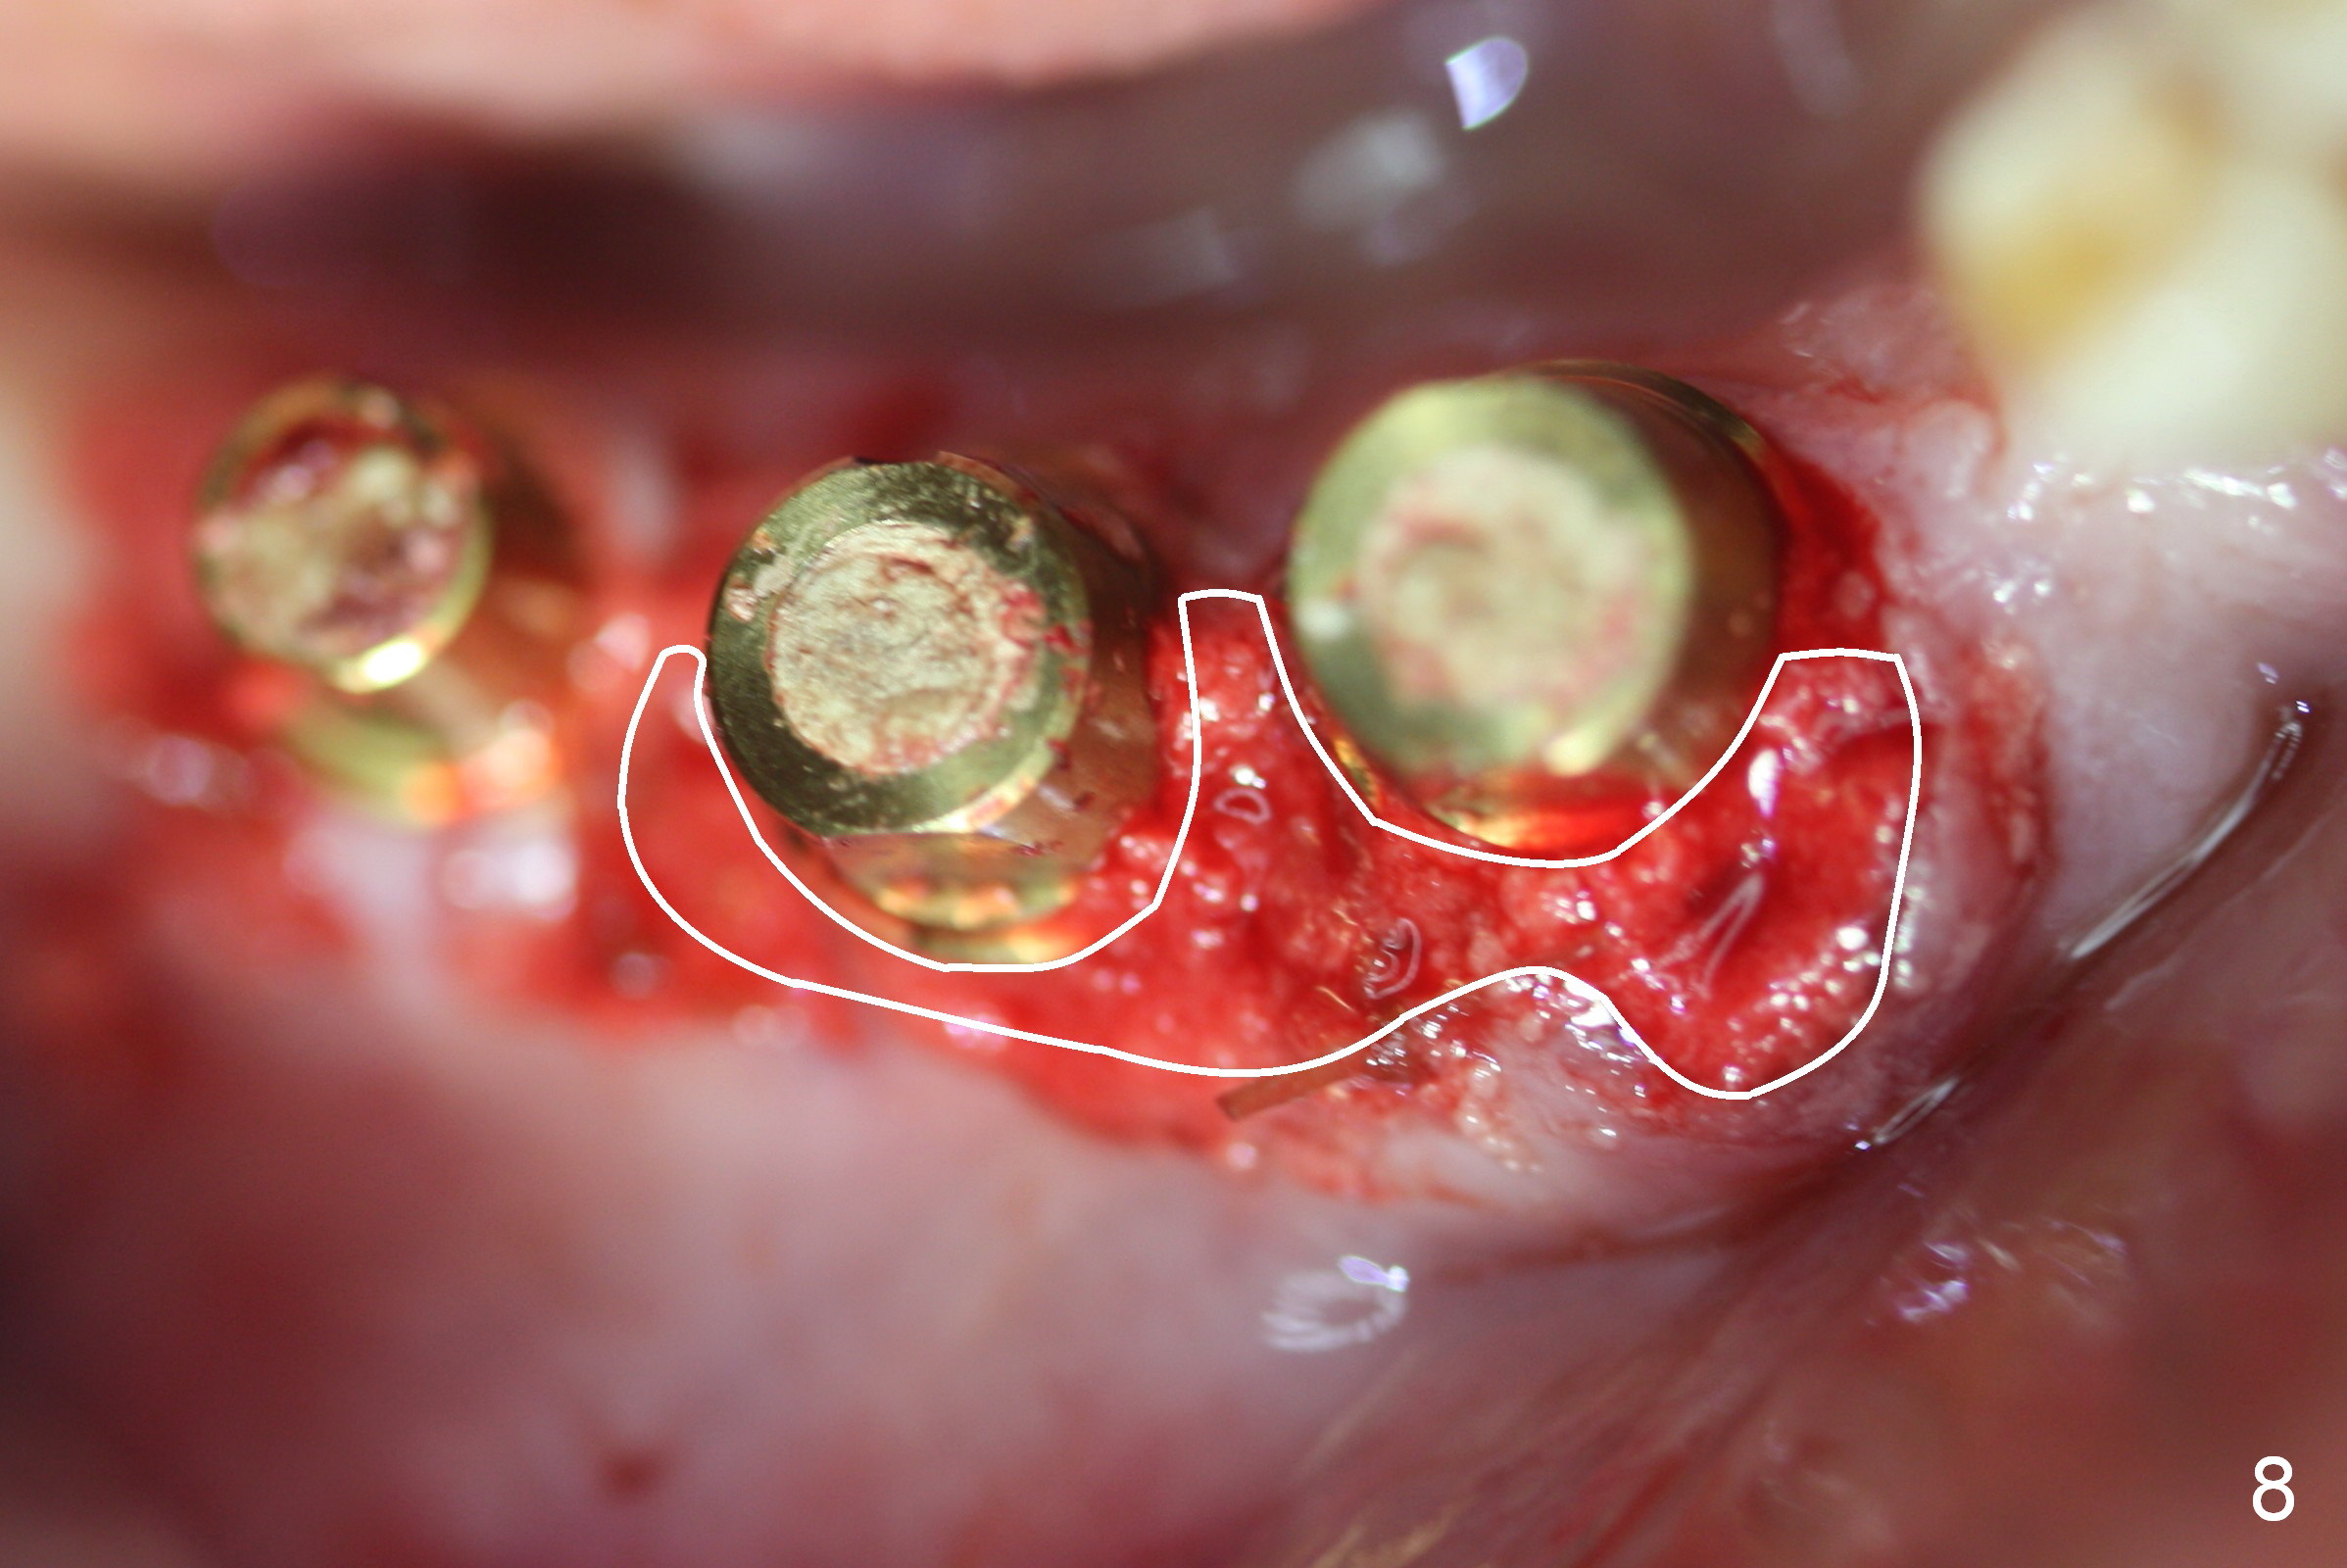

A 86-year-old man returns to office for the lower right quadrant reconstruction with implants. In addition to the immediate ones at the sites of #27 and 28 (Fig.1), how many and where else? The patient reveals that he does not plan to get an implant at the site of #3 (Fig.2). Therefore there is no need for an implant at #30. Preop CT shows that bone width is compromised at #26. So the 3rd site will be #29 (Fig.3,4). All of the 3 implants (4.5x14 mm, 4.5x12, and 4.1x12 mm) achieve primary stability (»55 Ncm). An immediate provisional could be provided, but it seems difficult to close the buccal (Fig.5 B) gaps of #27 and 28 after bone graft with the provisional. In contrast, the gingiva adapts to the implant at #29 well (Fig.6 B). Perio dressing is applied to the abutments (Fig. 7: #27-29), the edentulous space at #26 and the neighboring teeth (#23,24). It would be ideal to apply a non-resorbable membrane to the buccal opening at #27,28 (Fig.8 white line) prior to perio dressing placement. In case of dislodgement of the latter, the membrane is able to keep bone graft in place.